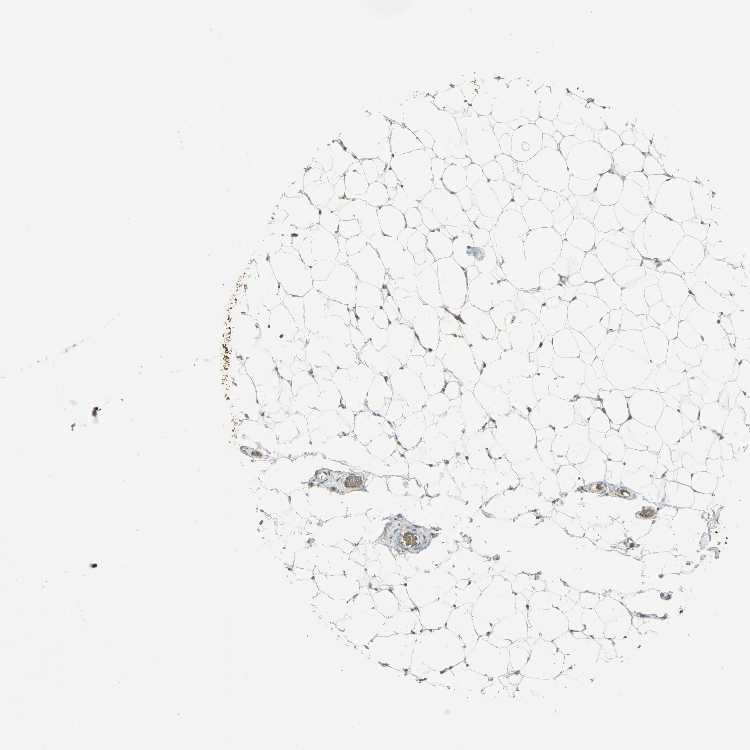

ADIPOSE TISSUE - Antibody stainingi

Antibody staining in the annotated cell types in the current human tissue is reported as not detected, low, medium, or high, based on conventional immunohistochemistry profiling in selected tissues. This score is based on the combination of the staining intensity and fraction of stained cells.

Each image is clickable and will lead to virtual microscopy that enables deeper exploration of all samples and also displays staining intensity scores, fraction scores and subcellular localization as well as patient and tissue information for each sample.

Antibody HPA006308Antibody HPA071064

Adipocytes MediumNot detected